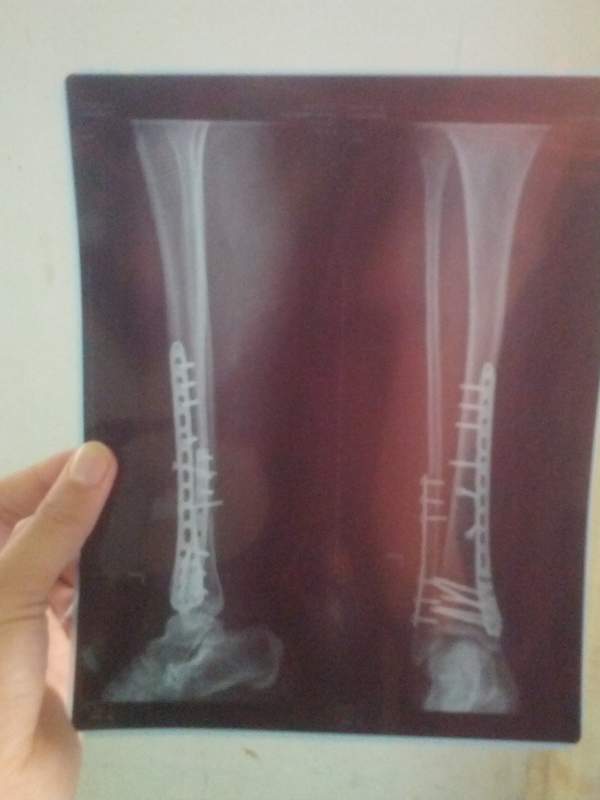

妈妈今年51岁,11月15号左胫腓骨骨折了,24号做了手术,加了两个钢板,现在脚还是肿的厉害。 请教问一下各位老师,现在需不需要开始做康复训练,可不可以麻烦各位老师帮忙制定一下。我把片子传上来 IMG_20141118_082401.jpg IMG_20141126_161505.jpg |